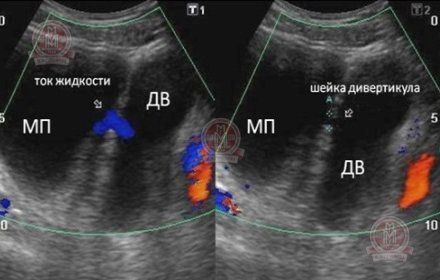

Малюнок №3 (УЗД) Типовий дивертикул сечового міхура - при доплерографії визначається струм рідини між сечовим міхуром (МП) і дивертикулом (ДВ).